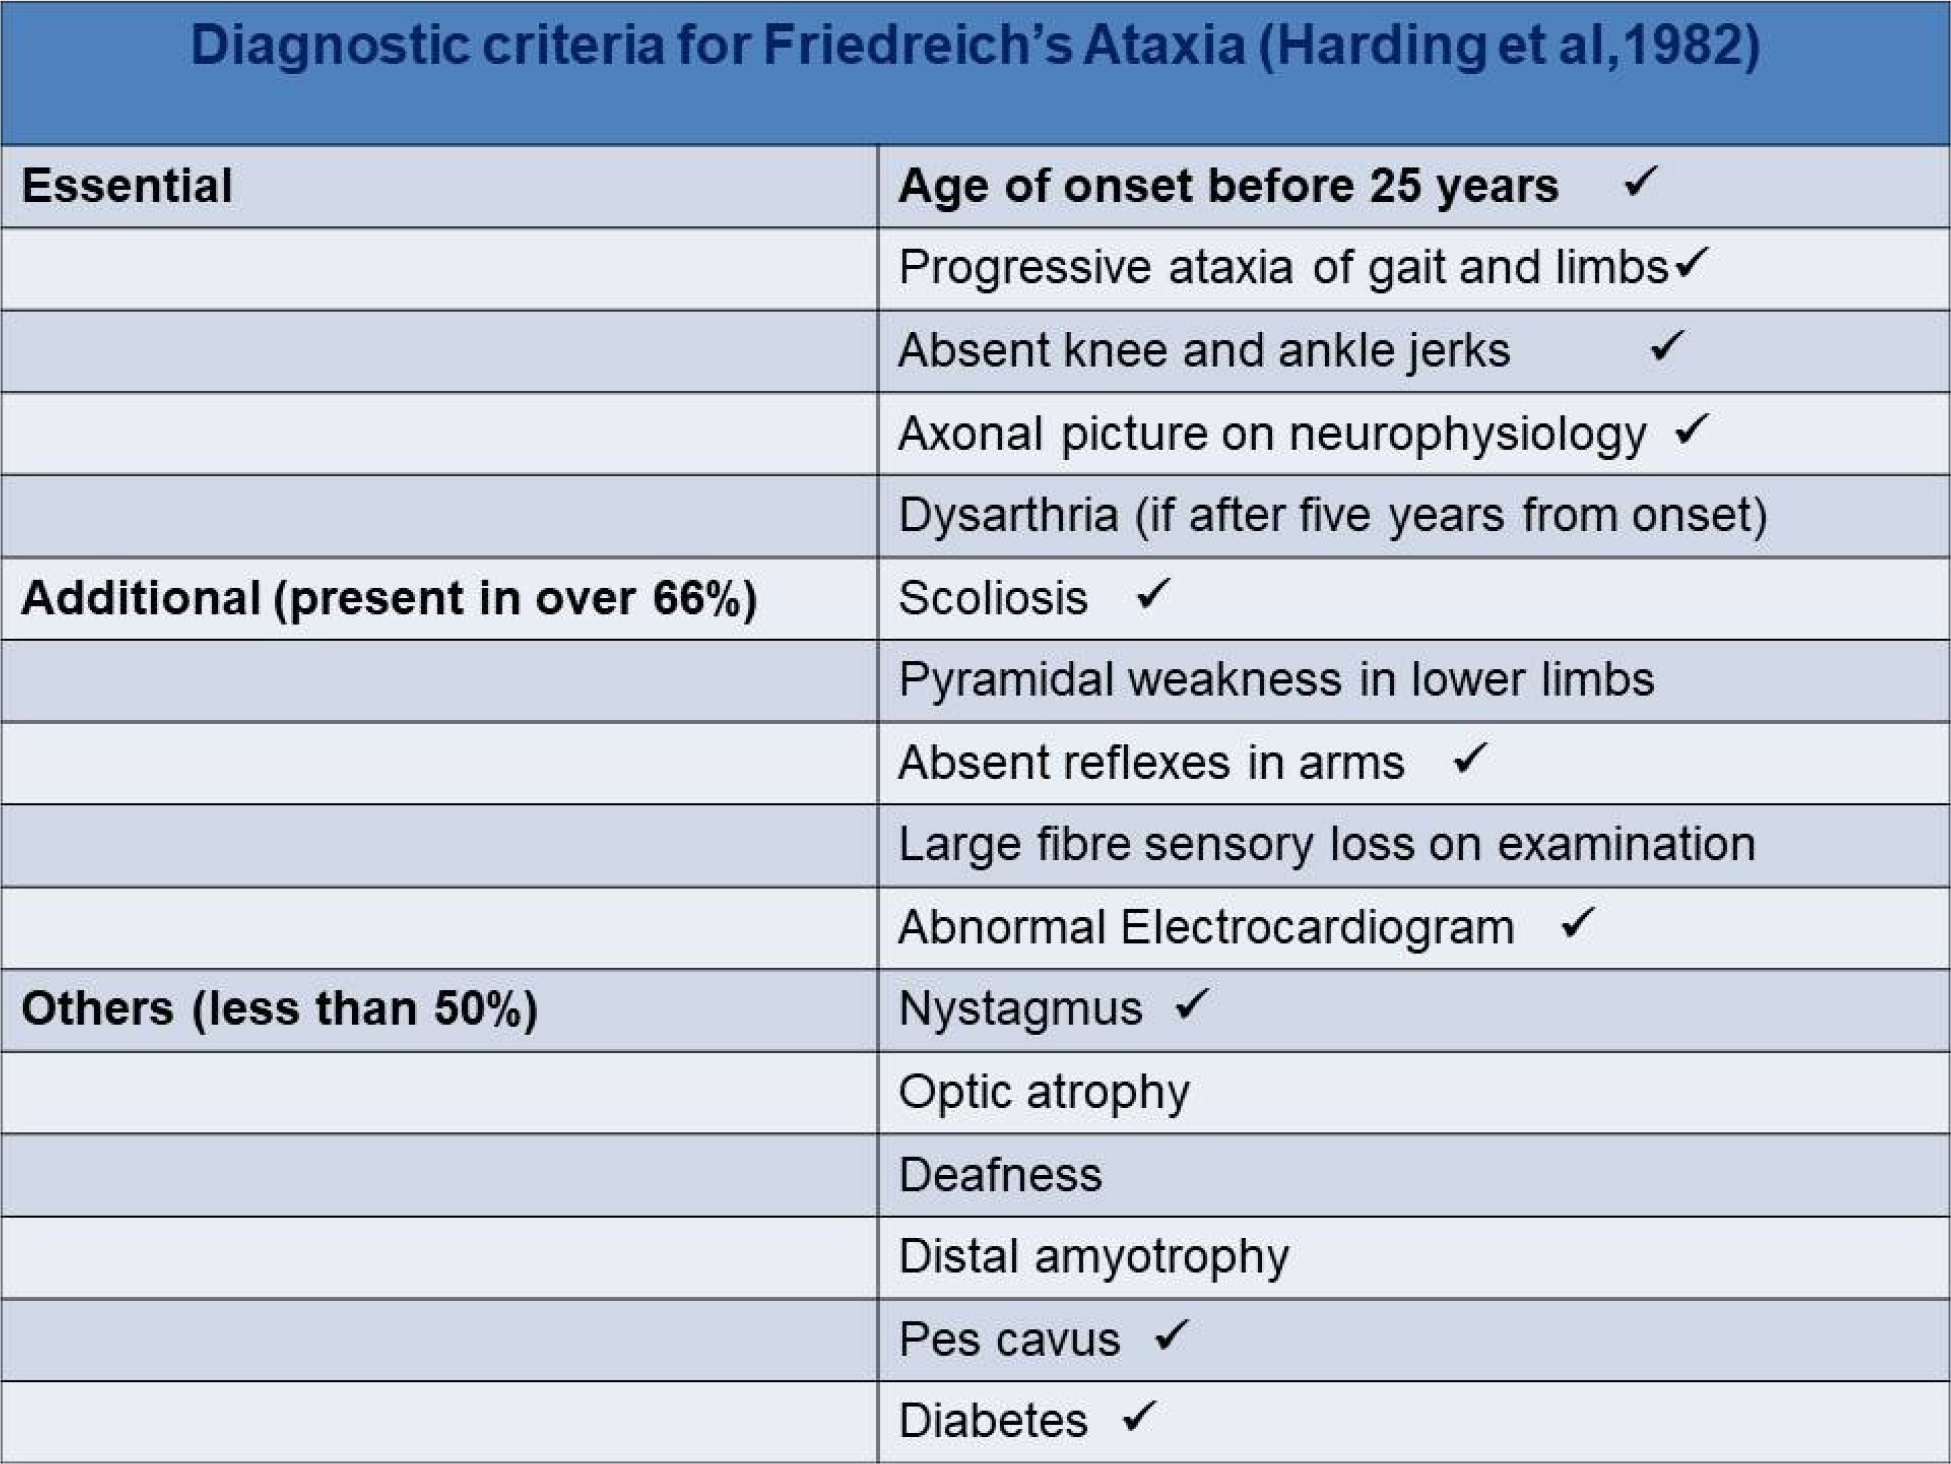

The patient had a staggering gait when ambulated. The genetic analysis was not done because of financial constraints. The diagnosis was confirmed based on criteria as per Harding et al. [2] of the skeletal (Figure 3). The patient was discharged in a stable condition.

Figure 3: Diagnostic criteria for Friedreich’s ataxia by Harding et al [2].

Tick marks indicate the features present in the case.